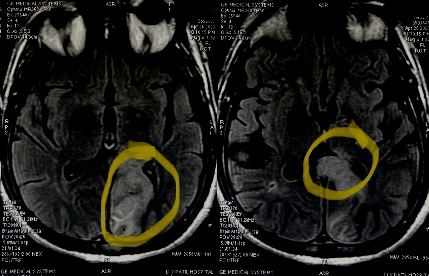

This gentleman woke up to realise he cannot read the newspaper He is able to write, but unable to read. What’s more fascinating?! He is unable to rea